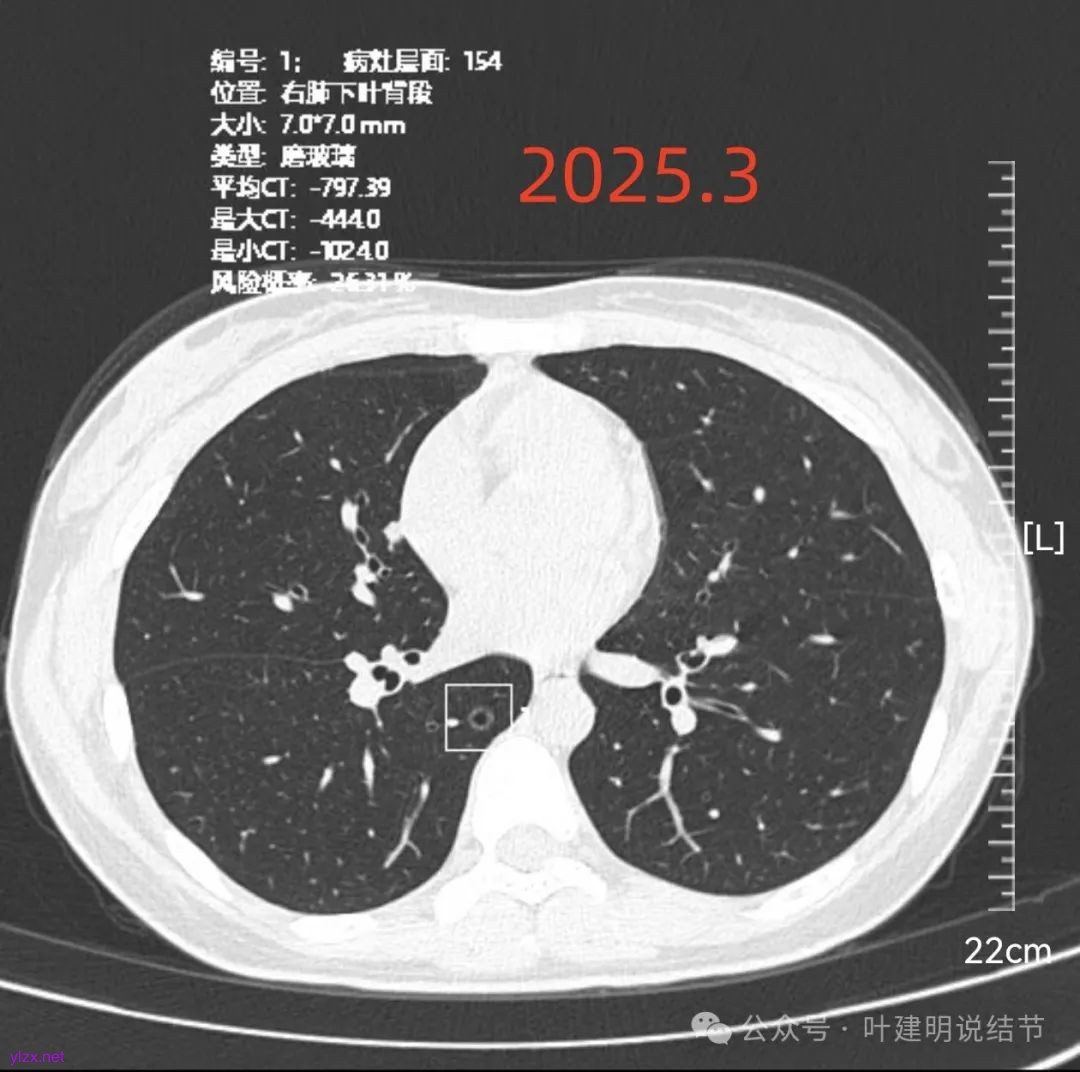

病灶6:右下叶脊柱旁囊腔型病灶,整体轮廓与边界清,没有明显实性成分,考虑原位癌或微浸润性腺癌可能性大。

再看2025年3月的影像:

各病灶均无明显吸收好转,但显然也说不上有明显进展。所以基本上要考虑是肿瘤范畴的(包括肺泡上皮不典型增生或肺泡上皮增生)。但危险性显然不算高,至少近2年了没有什么进展,即使病灶6最厉害的也是纯磨密度伴空腔。

再来看风险最大的病灶6的连续层面:

血管从旁过,没有受结节影响。